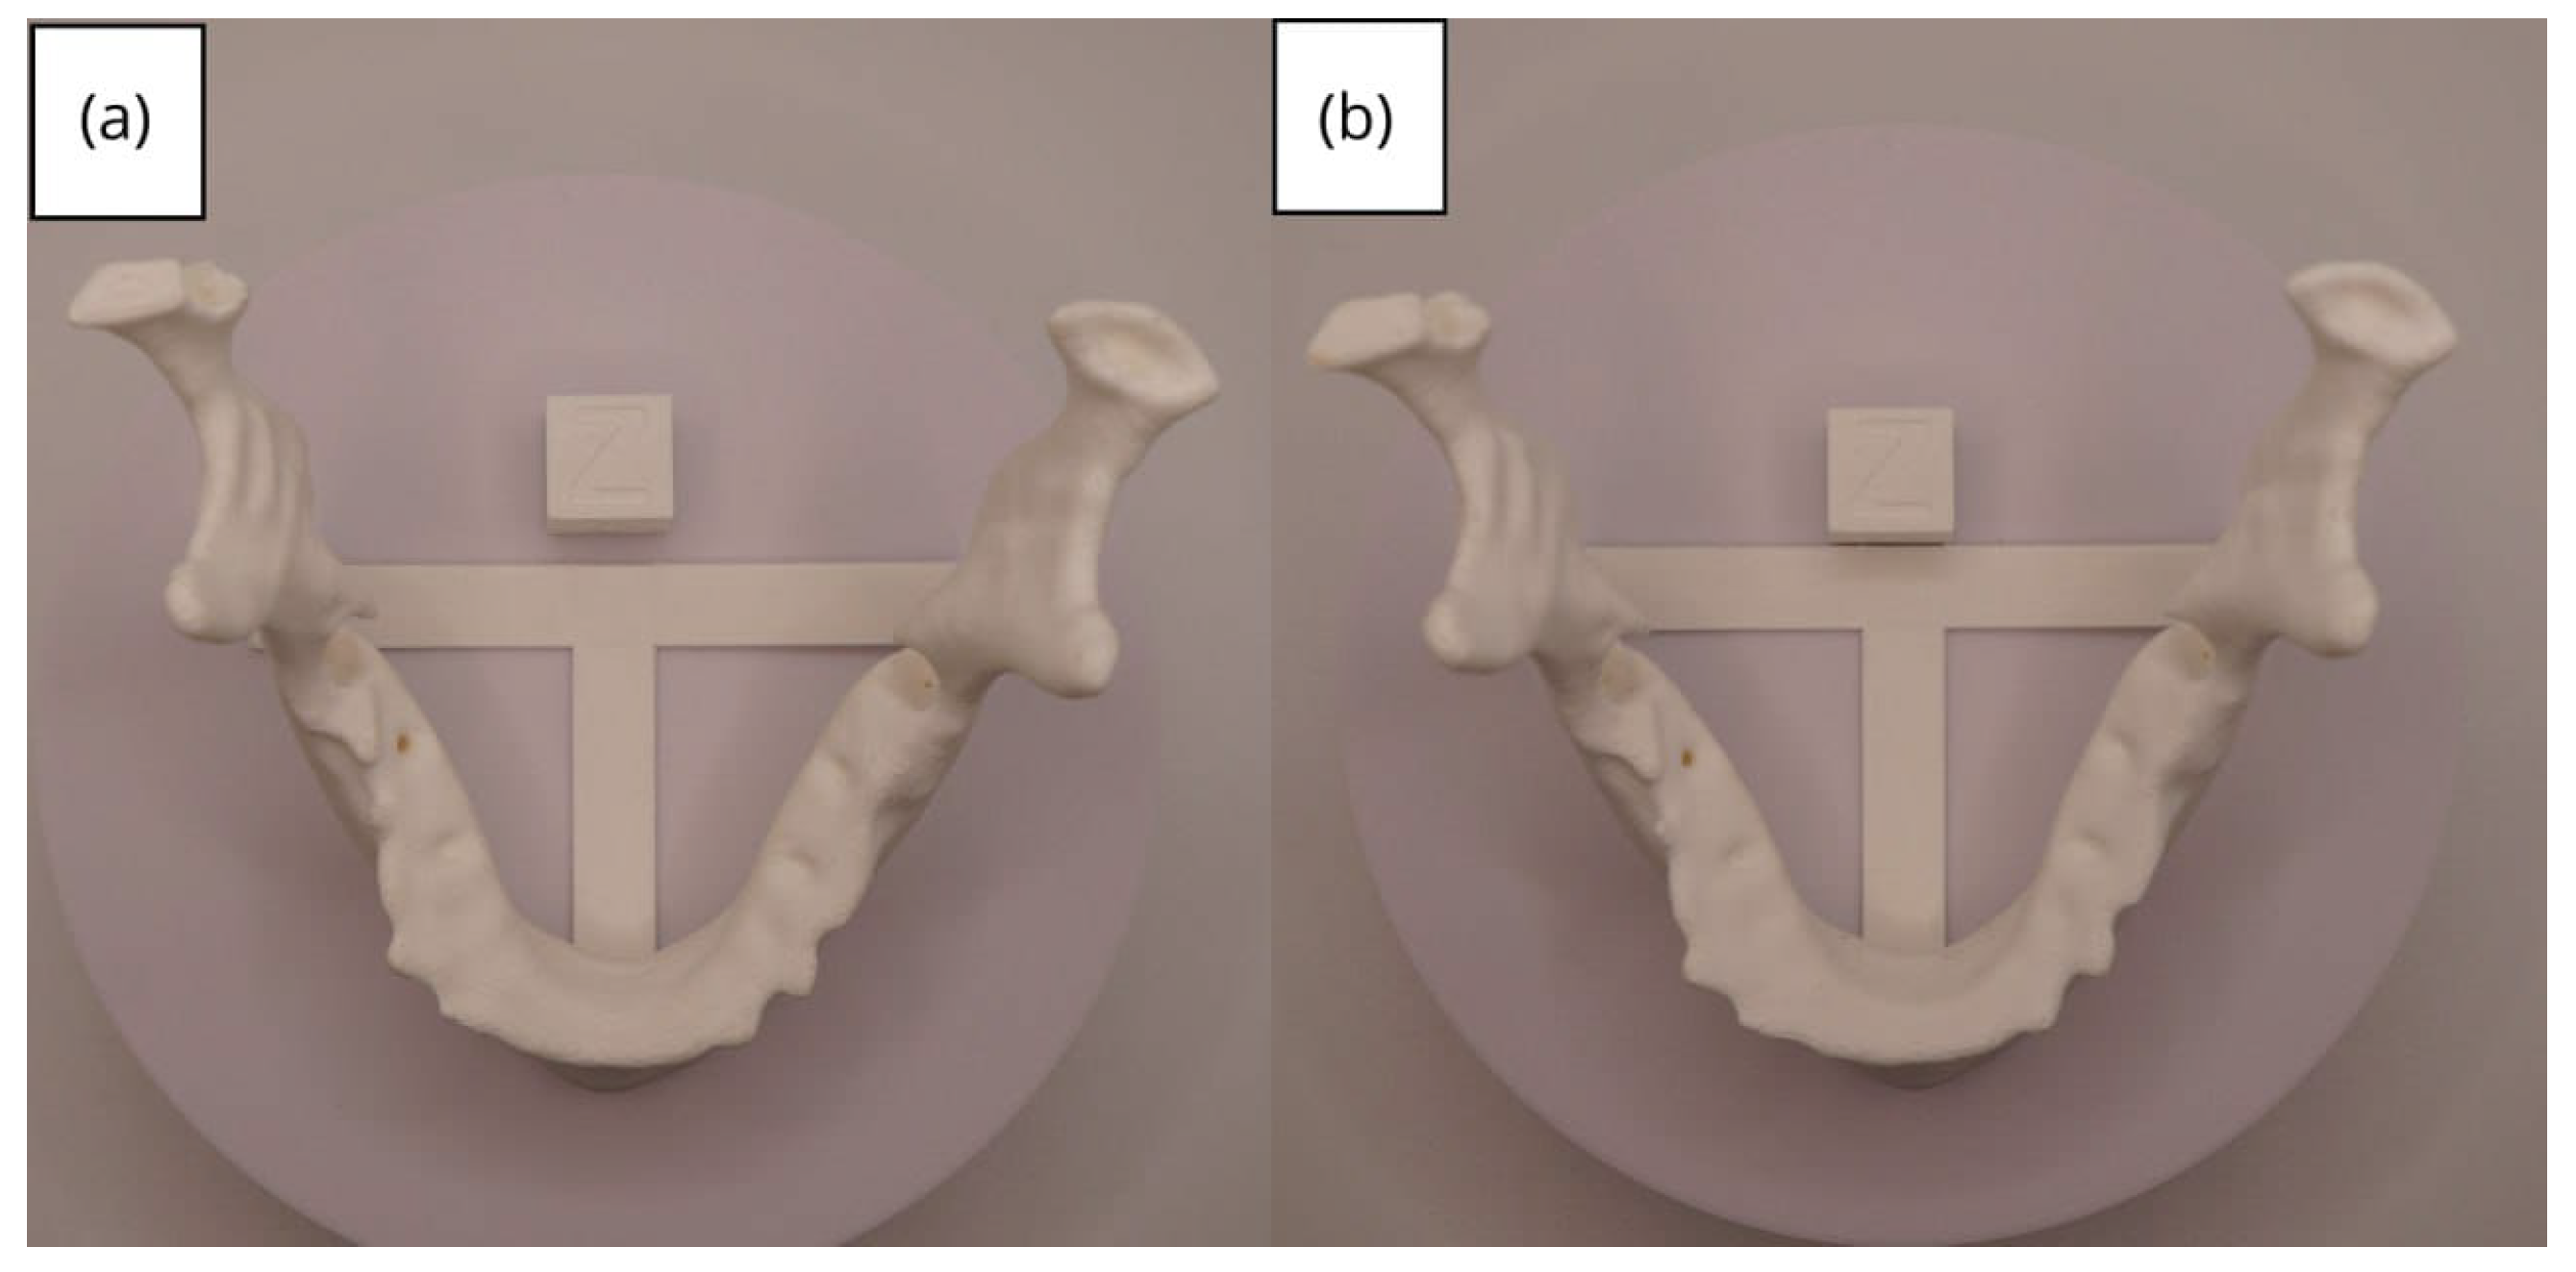

3.2. Human Lower Jaw

3.2.1. DICOM-to-STL Files

3.2.2. STL-to-GCODE Files

3.2.3. Final Printing

| Lower jaw models | m; m | Artillery Sidewinder X2 |

| m; m | Creality Ender 3 | |